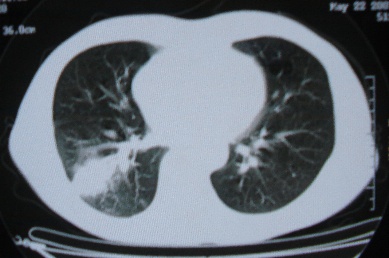

ct10716,男,59岁。发热咳嗽一天,咯血一次入院。

病灶中心有低密度,气体,病灶周围炎性浸润可能为肺脓肿,量体温、查个痰就是了,但肺脓肿一般都多少会有点兄水的。左肺下局部密度减低,小叶中心肺气肿。

病灶边缘较模糊,中心见低密度影及少量气影,宽基与胸膜相连,周围见炎性浸润,考虑右下肺脓肿。

病灶边缘较模糊,中心见低密度影及少量气影,宽基与胸膜相连,周围见炎性浸润,考虑右下肺脓肿。建议治疗后复查。

右下肺病灶,边缘模糊,中心见低密度坏死区及气体影,结合病史较短,以发热为主,考虑右下肺脓肿,建议抗炎治疗后复查。